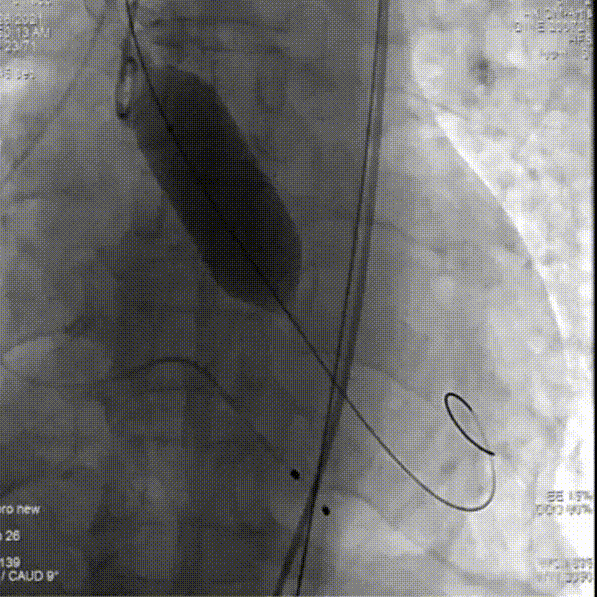

主动脉根部造影

球囊预扩

第一次尝试释放

位置偏深回收调整,进行第二次释放

瓣膜流入端被压缩有上跳风险,再一次进行回收

第三次释放

人工瓣有相应折叠,全部回收撤出体外

更换后瓣膜再一次进行释放

部分回收进行位置的微调整

完全释放后,主动脉根部造影